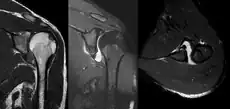

MRI of shoulder after dislocation with Hill-Sachs lesion and labral Bankart's lesion.

In young adults engaged in highly demanding activities shoulder surgery may be considered.[22] Arthroscopic surgery techniques may be used to repair the glenoidal labrum, capsular ligaments, biceps long head anchor or SLAP lesion or to tighten the shoulder capsule.[23]